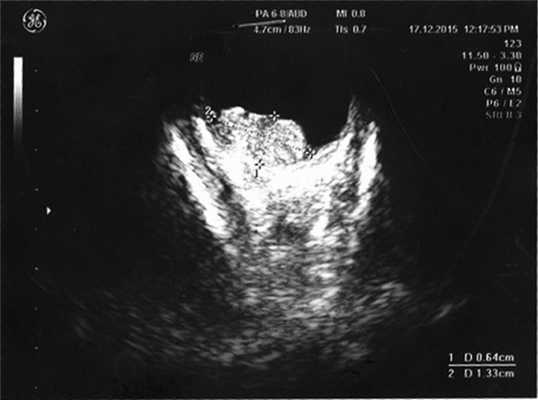

Согласно данным ультразвукового исследования, у заднего полюса выявлены плюс-ткань гетерогенной эхоструктуры с единичными кальцинатами, размером 6,4×13,3 мм, вторичная отслойка сетчатки (рис. 2). Учитывая локализацию опухоли (солитарный опухолевый узел, полностью перекрывающий ДЗН), отсутствие шансов на зрение, размеры образования и высокий риск экстрабульбарного распространения опухоли, выполнена энуклеация левого глаза с пластикой культи. После получения патогистологического заключения (злокачественная медуллоэпителиома) ребенок направлен на консультацию к детскому онкологу с целью возможного выявления новообразования в головном мозге. По данным магнитно-резонансной томографии, опухолевых очагов в ЦНС не выявлено, однако в связи с прорастанием опухоли за laminacribrosa пациенту назначен курс лучевой и химиотерапии (циклофосфан, вепезид, карбоплатин).

Рис. 2. Результат эхографии левого глаза у ребенка с подозрением на монокулярную форму ретинобластомы.